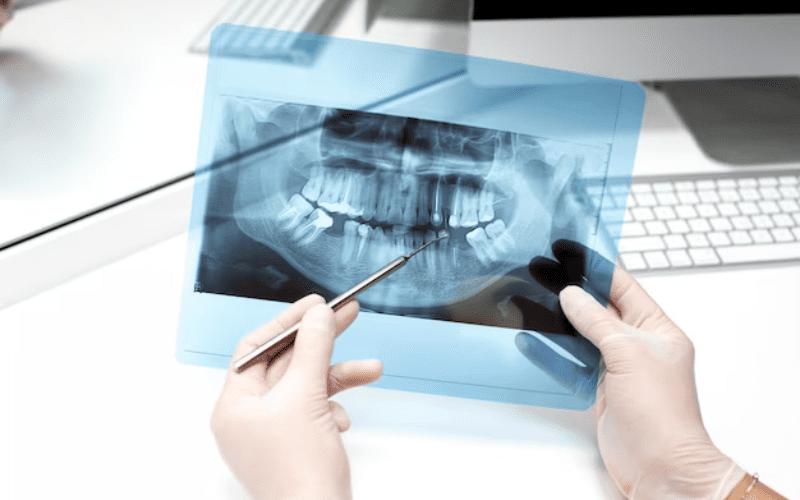

What Is Dental Radiology? Dental Radiology is the specialized field of dentistry focused on diagnostic imaging of the teeth, jaw, and surrounding oral structures. It